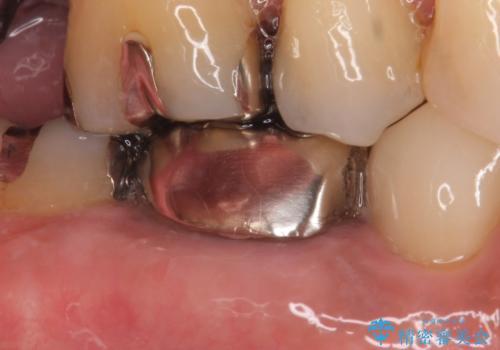

- ものを咬むと右下の奥歯が疼くといらっしゃった方の症例です。

検査の結果X線上で右下6に根尖病変を認めたため、再根管治療を行いました。

症状が治まったのを確認後、オールセラミッククラウンによる補綴を行いました。